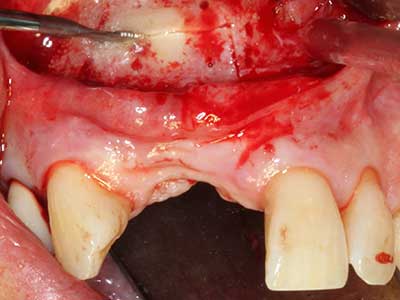

Knochengewebe ist nicht nur rein mineralisch, sondern auch in wesentlichen Anteilen aus Kollagenfasern aufgebaut. Dies gewährleistet neben einer guten Druckfestigkeit eine gewisse Flexibilität, welche für die Durchführung von Augmentationen genutzt werden kann. Bei der klassischen Expansionsplastik im Sinne eines Bone Splittings wird der atrophierte Kieferkamm in seiner Längsachse gespalten und nach Erreichen einer ausreichenden Osteotomietiefe vorsichtig aufgedehnt (Abb. 13-16), idealerweise ohne den Kiefer wesentlich zu deperiostieren (Brugnami, Caiazzo et al. 2014, Stricker, Fleiner et al. 2014). Bewährt haben sich Schrauben- und Plattensysteme mit zunehmender Expansionsdistanz, um die beiden Knochenlamellen unterhalb der Bruchschwelle voneinander zu distanzieren. In der Regel werden Restknochenbreiten von mindestens 3-4 mm gefordert (Chiapasco, Zaniboni et al. 2006), um eine ausreichende Flexibilität und knöcherne Bedeckung der einzubringenden Implantate zu gewährleisten. Ggf. kann eine ein- oder beidseitige vertikale Entlastungsosteotomie die Flexibilität verbessern. Als Alternative zur klassischen Technik wurde eine Kombination mit weiteren augmentativen Techniken vor allem auf der bukkalen Seite beschrieben.

Mittels Piezosägen erfolgt die Anlage des Splittings besonders schonend und ohne wesentliche Dimensionsverluste, so dass sich keine signifikanten Unterschiede von Implantaten im gesplitteten Kiefer im Vergleich zum nicht defizitären Alveolarkamm gezeigt haben (Chiapasco, Zaniboni et al. 2006, Danza, Guidi et al. 2009). Gerade beim lokal begrenzten und tiefen Splitting ist jedoch stets auf eine ausreichende Wasserkühlung zu achten, um thermische Belastungen in den apikalen Osteotomiebereichen zu vermeiden.

Abb. 13: Bei diesem 52-jährigen Patienten ist bei 4 mm UK-Restknochenbreite während des Bone Splittings auf eine ausreichende Wasserkühlung zu achten.